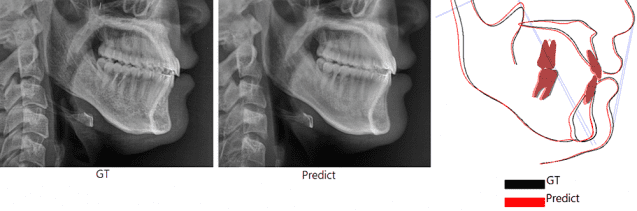

이번 AI 모델의 정확도를 검증한 결과, 연구에 참여한 교정 전문의와 구강악안면외과 전문의들은 AI가 생성한 예측 영상과 실제 수술 후 촬영한 영상을 구분하지 못했으며, 두 영상에 표시된 해부학적 기준점(계측점) 간의 평균 오차는 대부분 1.5㎜ 이하일 정도로 매우 높은 정확도를 보인 것으로 나타났다.

AI 모델의 예측 정확도를 검증하기 위해 교정 전문의 2명과 구강악안면외과 전문의 2명이 AI가 생성한 영상과 실제 수술 후 촬영된 영상을 구별할 수 있는지 확인했는데, 둘 중 AI가 생성한 영상을 구분해낸 비율은 48%를 기록해 두 영상을 거의 구분하지 못한 것으로 나타났다.

AI가 예측한 영상과 실제 수술 후 영상의 계측점 간 평균 오차는 대부분 1.5㎜ 이하였다. 이는 같은 대상을 두 번 측정할 때 발생하는 오차와 유사한 수준으로, 의료 현장에서 활용될 수 있을 만큼의 정밀도를 확보한 것으로 평가된다.